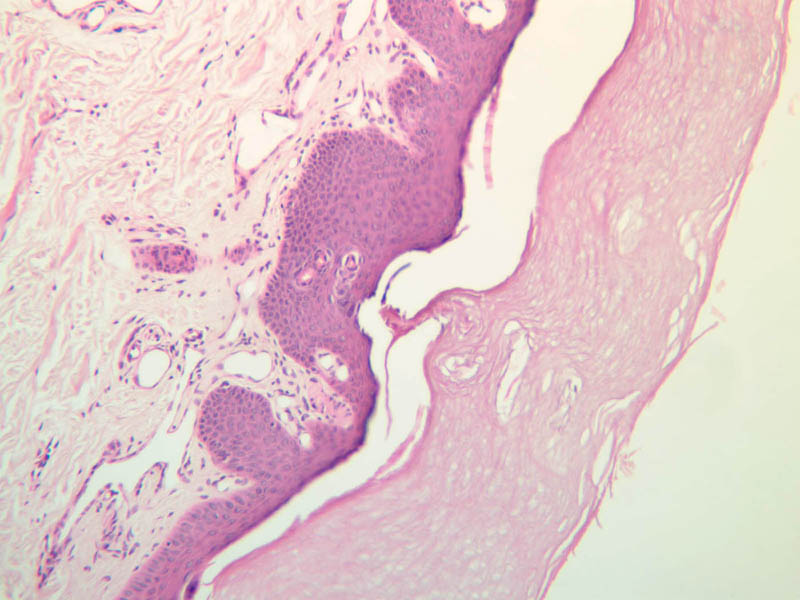

For general orientation, note that skin has two components, epidermis (a stratified squamous epithelium) and dermis (a connective tissue layer beneath the epidermis). Epidermal ridges project into the dermis, enclosing between them the highly vascular dermal papillae. Beneath the dermis lies the subcutaneous tissue, a loose layer of connective tissue, fat, blood vessels, and nerves. The skin appendages are situated partially in the dermis and partially in the subcutaneous layer. The skin consists primarily of two cell types; a keratin-producing epithelial cell (keratinocytes) and a pigment cell of neural crest origin (melanocyte). Langerhans cells are also present. These are believed to be antigen presenting cells of the epidermis. The keratinocytes exhibit morphological and functional stratification from base to surface of the epithelium and thus provide a basis for distinguishing several layers of the epidermis.

Examine slide A-50 (fingertip, H&E [2.5x, 10x-labeled, 20x, 40x-labeled] [20x, 40x] [10x, 20x, 40x] [20x, 20x, 40x]), and study the morphology of five layers of thick skin. The deepest part of the epidermis comprises the stratum basale which provides the cells required for continual renewal of the epidermis. This stratum is composed of a single layer of columnar or cuboidal epithelial cells attached to the basement membrane.

The stratum lucidum is often considered to be a subdivision of the stratum corneum. This layer is evident only in thick (glaborous) skin. It appears as a clear band beneath the stratum corneum. Cells of the stratum lucidum are well advanced in the process of keratinization. Consequently, the nucleus and many of the cytoplasmic organelles become disrupted and disappear as the cells become filled with the intracellular protein keratin. In many specimens, there is a separation artifact at this point. The outermost layer of the epidermis is called the stratum corneum and is composed of fully cornified (keratinized) remnants of epithelial cells ([40x]). It has a basketweave appearance. The close union of the resulting scales with each other, and their content of insoluble protein and extracellular lipids, provides a barrier to diffusion between the body and its external environment.